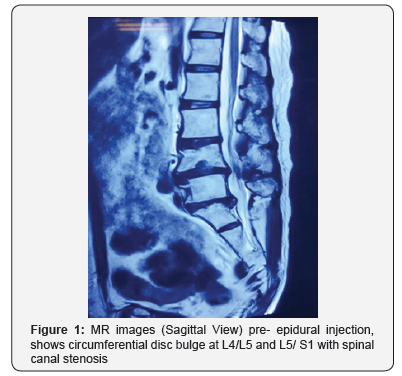

Ms M, a 62 year- old lady was diagnosed clinically with lumbar canal stenosis L4/L5 and L5/S1, she has been treated conservatively with pharmacological and physical therapy but failed. X- ray of the lumbosacral spine showed degenerative changes of the lower lumbar region. Magnetic resonance imaging (MRI) revealed worst stenosis at L5/S1 (Figure 1-3). She was subsequently scheduled for an epidural steroid injection. Prior to the epidural injection, she was able to ambulate unaided, the bowel and bladder functions were normal and clinically the neurological status of bilateral lower limbs was intact. Anepidural injection was performed at the level of L3/L4. A total of 1ml chirocaine (Levobupivacaine HCL 5.0mg) and 1ml diprospan (betamethasone dipropionate 5mg, betamethasone disodium phosphate 2mg) was given in a single attempt. No blood or cerebrospinal fluid was aspirated prior to administration of the drugs.

Her symptoms however continued to persist even after 24 hours to which an MRI was done to rule out epidural hematoma formation. The MRI reveals no extradural mass or hematoma collection. It was unremarkable as compared to the pre- epiduralinjection MR images (Figure 4-6). All other blood investigations and imaging was also normal. She subsequently underwent an emergency laminectomy of the L4/L5 and L5/S1 level after 6 days of observation for spontaneous neurological recovery. Intraoperative findings reveal no hematoma and upon laminectomy, the dura bulge outwards (Figure 7).